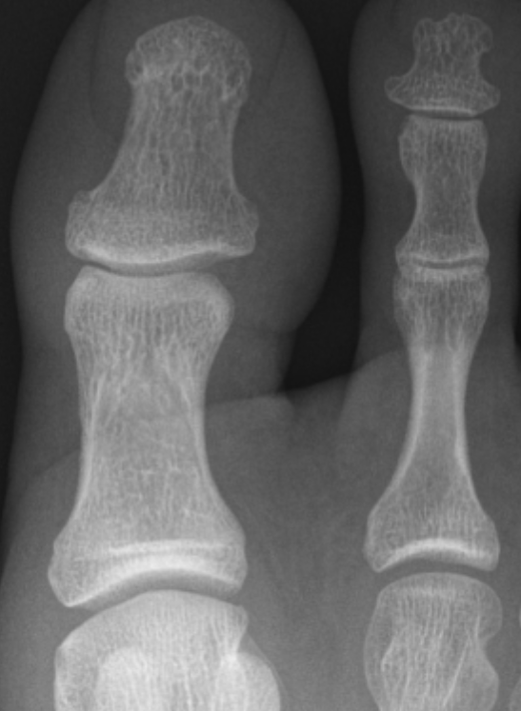

図2.足趾の単純X線

末節骨末端骨吸収像

と骨新生像